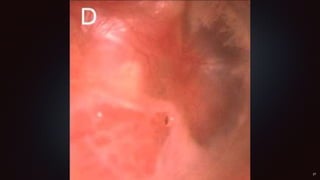

Otoscopie

Oreille Droite ou Gauche ?

Quelle est l’anomalie ?

Otoscopie Oreille Droite ouGauche ? Quelle est l’anomalie ?